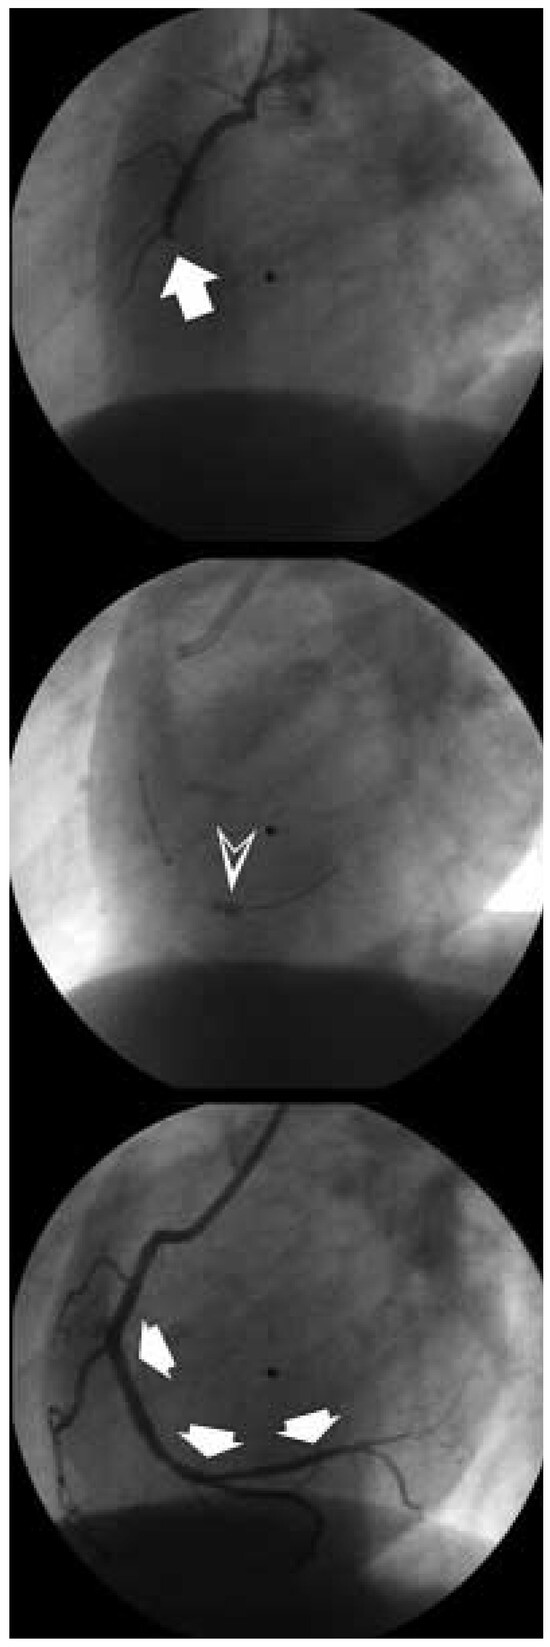

Bei Patienten mit akutem Koronarsyndrom und anderen Veränderungen im EKG (ST-Senkungen, T-Inversionen) oder nur vorüber gehenden Ruheschmerzen, kann die Interven tion in Ruhe, aber doch möglichst innerhalb der nächsten 24 Stunden erfolgen. Verschiedene Studien haben gezeigt, dass der Vorteil einer interventionellen Therapie vor allem bei Patienten mit einer Erhöhung des Troponins nachweisbar ist (Abb. 5) [10,11,12]. Eine perku tane koronare Intervention erfolgt heute di rekt nach angiographischer Darstellung der infarktbezogenen Arterie. Bei Patienten mit Totalverschluss der Herzkranzarterie und sichtbaren Thromben empfiehlt sich ein Ab saugen des Thrombusmaterials mittels eines intrakoronaren Saugkatheters (Abb. 6) [13]. Verschiedene Untersuchungen haben gezeigt, dass ein guter Koronarfluss nach der Inter vention prognostisch für den weiteren Verlauf des Patienten bedeutsam ist [14, 15]. Der Erfolg akuter perkutaner Interventionen – bis in die 1990er Jahre noch ein Tabu der inter ventionellen Kardiologie – wurde nur möglich durch die Einführung der Glykoprotein-IIb/IIIa-Antagonisten, welche den «final com mon pathway» der Thrombozytenaktivierung praktisch komplett hemmen [16, 17]. Dazu stehen neben Antikörpern wie Abciximab, der «lead compound» dieser Klasse, heute auch synthetische Moleküle wie Tirofiban und Eptifibatide zur Verfügung.

Figure 6. Perkutane koronare Inter vention bei einer verschlos senen rechten Koronararterie (Pfeil oben). Das temporäre Occlusions- und Aspirations-Device (PercuSurge®, Guard-Wire®) ermöglicht aufgrund eines kleinen aufblasbaren Ballons an der Spitze des Führungsdrahtes (™) eine Thrombusaspiration unter Protektion peripherer Koro-naräste (Pfeil Mitte). Nach der Intervention besteht ein guter Fluss (Pfeile unten).